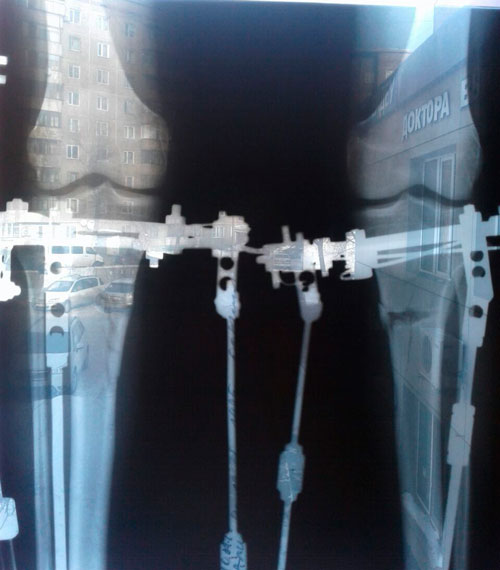

Дата операции 20.12.2016г.

Дата снятия аппаратов 04.03.2017г.

Срок лечения 71 день.